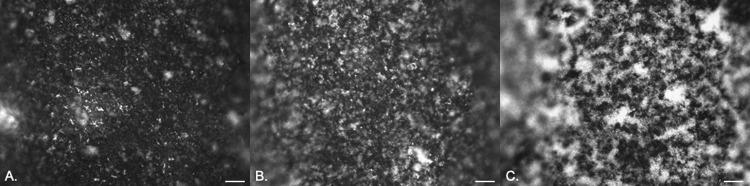

Catheter-associated urinary tract infections have serious consequences, for both patients and health care resources. Much work has been carried out to develop an antimicrobial catheter. Although such developments have shown promise under laboratory conditions, none have demonstrated a clear advantage in clinical trials. Using a range of microbiological and advanced microscopy techniques, a detailed laboratory study comparing biofilm development on silicone, hydrogel latex, and silver alloy-coated hydrogel latex catheters was carried out. Biofilm development by , , and on three commercially available catheters was tracked over time. Samples were examined with episcopic differential interference contrast (EDIC) microscopy, culture analysis, and staining techniques to quantify viable but nonculturable (VBNC) bacteria. Both qualitative and quantitative assessments found biofilms to develop rapidly on all three materials. EDIC microscopy revealed the rough surface topography of the materials. Differences between culture counts and quantification of total and dead cells demonstrated the presence of VBNC populations, where bacteria retain viability but are not metabolically active. The use of nonculture-based techniques showed the development of widespread VBNC populations. These VBNC populations were more evident on silver alloy-coated hydrogel latex catheters, indicating a bacteriostatic effect at best. The laboratory tests reported here, which detect VBNC bacteria, allow more rigorous assessment of antimicrobial catheters, explaining why there is often minimal benefit to patients. Several antimicrobial urinary catheter materials have been developed, but, although laboratory studies may show a benefit, none have significantly improved clinical outcomes. The use of poorly designed laboratory testing and lack of consideration of the impact of VBNC populations may be responsible. While the presence of VBNC populations is becoming more widely reported, there remains a lack of understanding of the clinical impact or influence of exposure to antimicrobial products. This is the first study to investigate the impact of antimicrobial surface materials and the appearance of VBNC populations. This demonstrates how improved testing is needed before clinical trials are initiated.

导管相关尿路感染会对患者和医疗资源造成严重后果。为了开发抗菌导管,已经开展了大量工作。尽管这些研究在实验室条件下显示出了一定的前景,但在临床试验中没有一项研究显示出明显的优势。本研究使用一系列微生物学和先进显微镜技术,对硅胶、水凝胶乳胶和银合金涂层水凝胶乳胶导管上生物膜形成进行了详细的实验室比较研究。通过时间追踪,研究了 在三种市售导管上的生物膜形成情况。使用相差微分干涉对比(EDIC)显微镜、培养分析和染色技术对样本进行检查,以量化活但非可培养(VBNC)细菌。定性和定量评估都发现生物膜在所有三种材料上都迅速形成。EDIC 显微镜揭示了材料粗糙的表面形貌。培养计数和总细胞及死亡细胞定量之间的差异表明存在 VBNC 群体,这些细菌仍具有活力但无代谢活性。非培养技术的使用显示出广泛的 VBNC 群体的发展。在银合金涂层水凝胶乳胶导管上,VBNC 群体更为明显,这表明最好是具有抑菌作用。这里报告的实验室测试可以检测 VBNC 细菌,从而更严格地评估抗菌导管,这解释了为什么对患者的益处通常很小。已经开发了几种抗菌导尿管材料,但尽管实验室研究可能显示出益处,但没有一种显著改善了临床结果。使用设计不佳的实验室测试且没有考虑 VBNC 群体的影响可能是原因之一。虽然 VBNC 群体的存在报告越来越多,但对其临床影响或接触抗菌产品的影响仍缺乏了解。这是第一项研究抗菌表面材料和 VBNC 群体出现的影响的研究。这表明在启动临床试验之前,需要进行改进的测试。